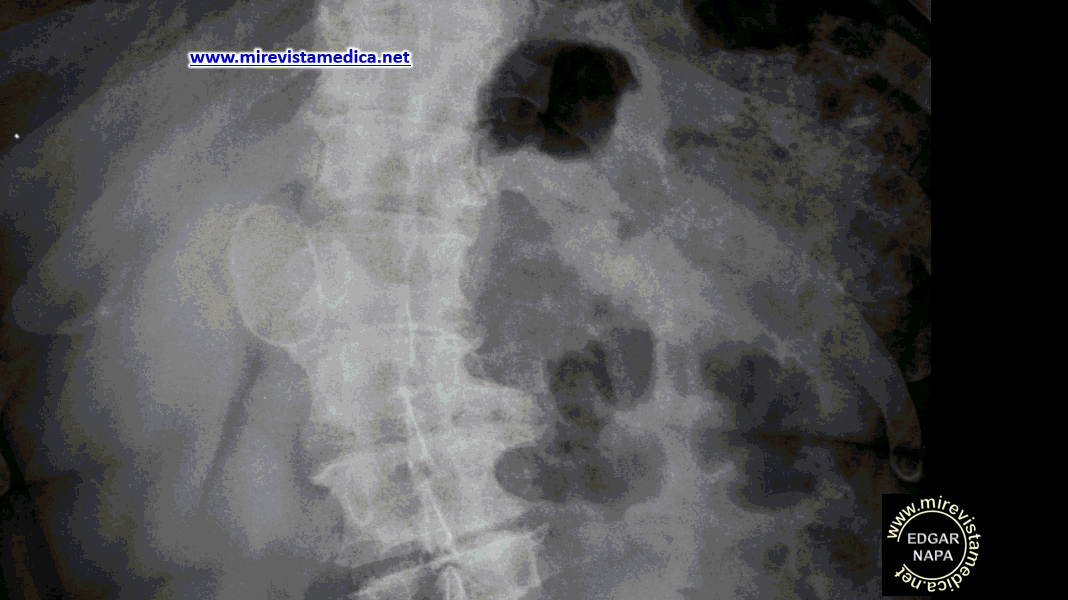

Radiografía de abdomen simple, de pie, vista sagital, muestra imagen radiopaca de forma oval.

Radiografía de abdomen simple, de pie, vista frontal , muestra imagen radiopaca de forma oval, a la derecha de la columna vertebral.